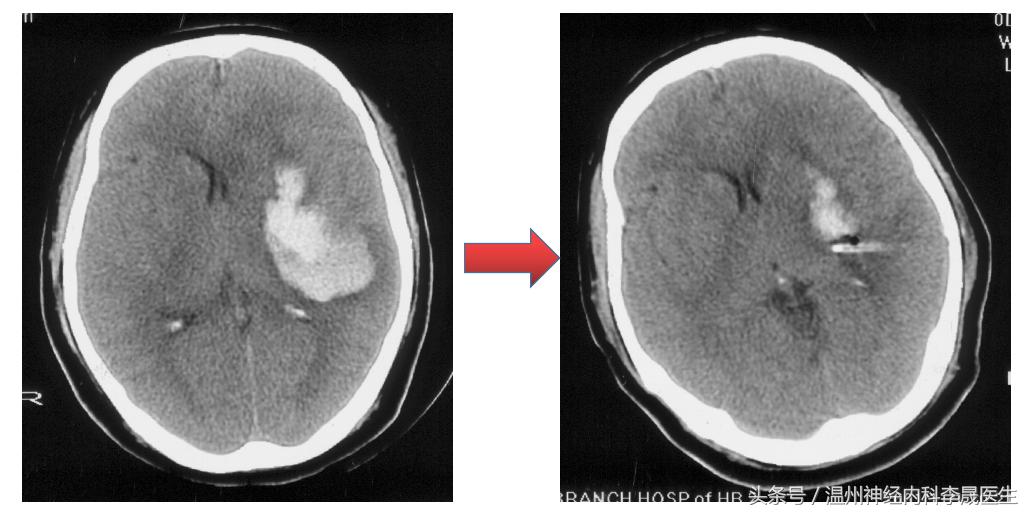

血肿量计算法。血肿量=长×宽×层面×π/6

脑出血CT全图

最大层面测量图

选取血肿最大层面,测量长宽径线,如果在胶片中,可以比对下方的刻度,一小格为1 cm。

出血量≈4.90×5.74×5.0÷2≈70 ml,但未包括破入脑室的出血量。